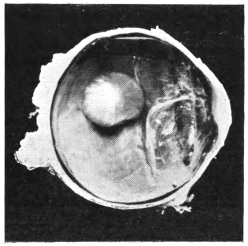

LENS DISLOCATED BETWEEN CILIARY BODY AND SCLERA

curly bracket span

11.

NUCLEUS OF CATARACT FREELY MOVABLE BETWEEN THE AQUEOUS AND VITREOUS CHAMBERS